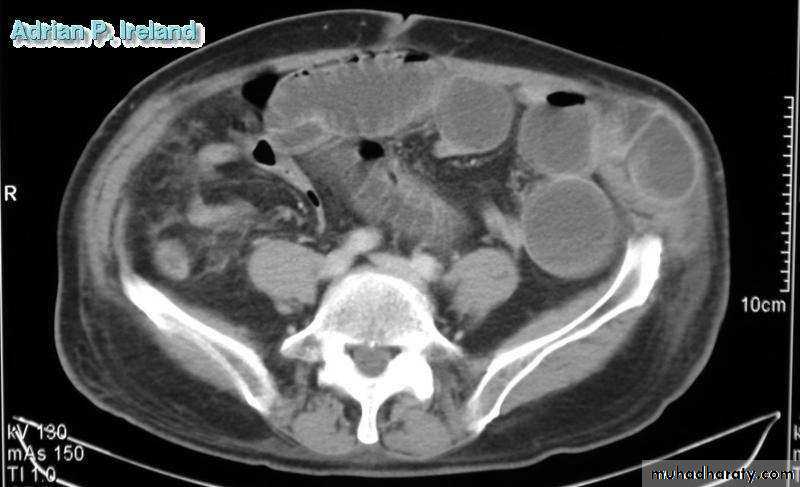

• Radiology; CT, Small bowel obstruction

• Operative Findings; Small bowel obstruction